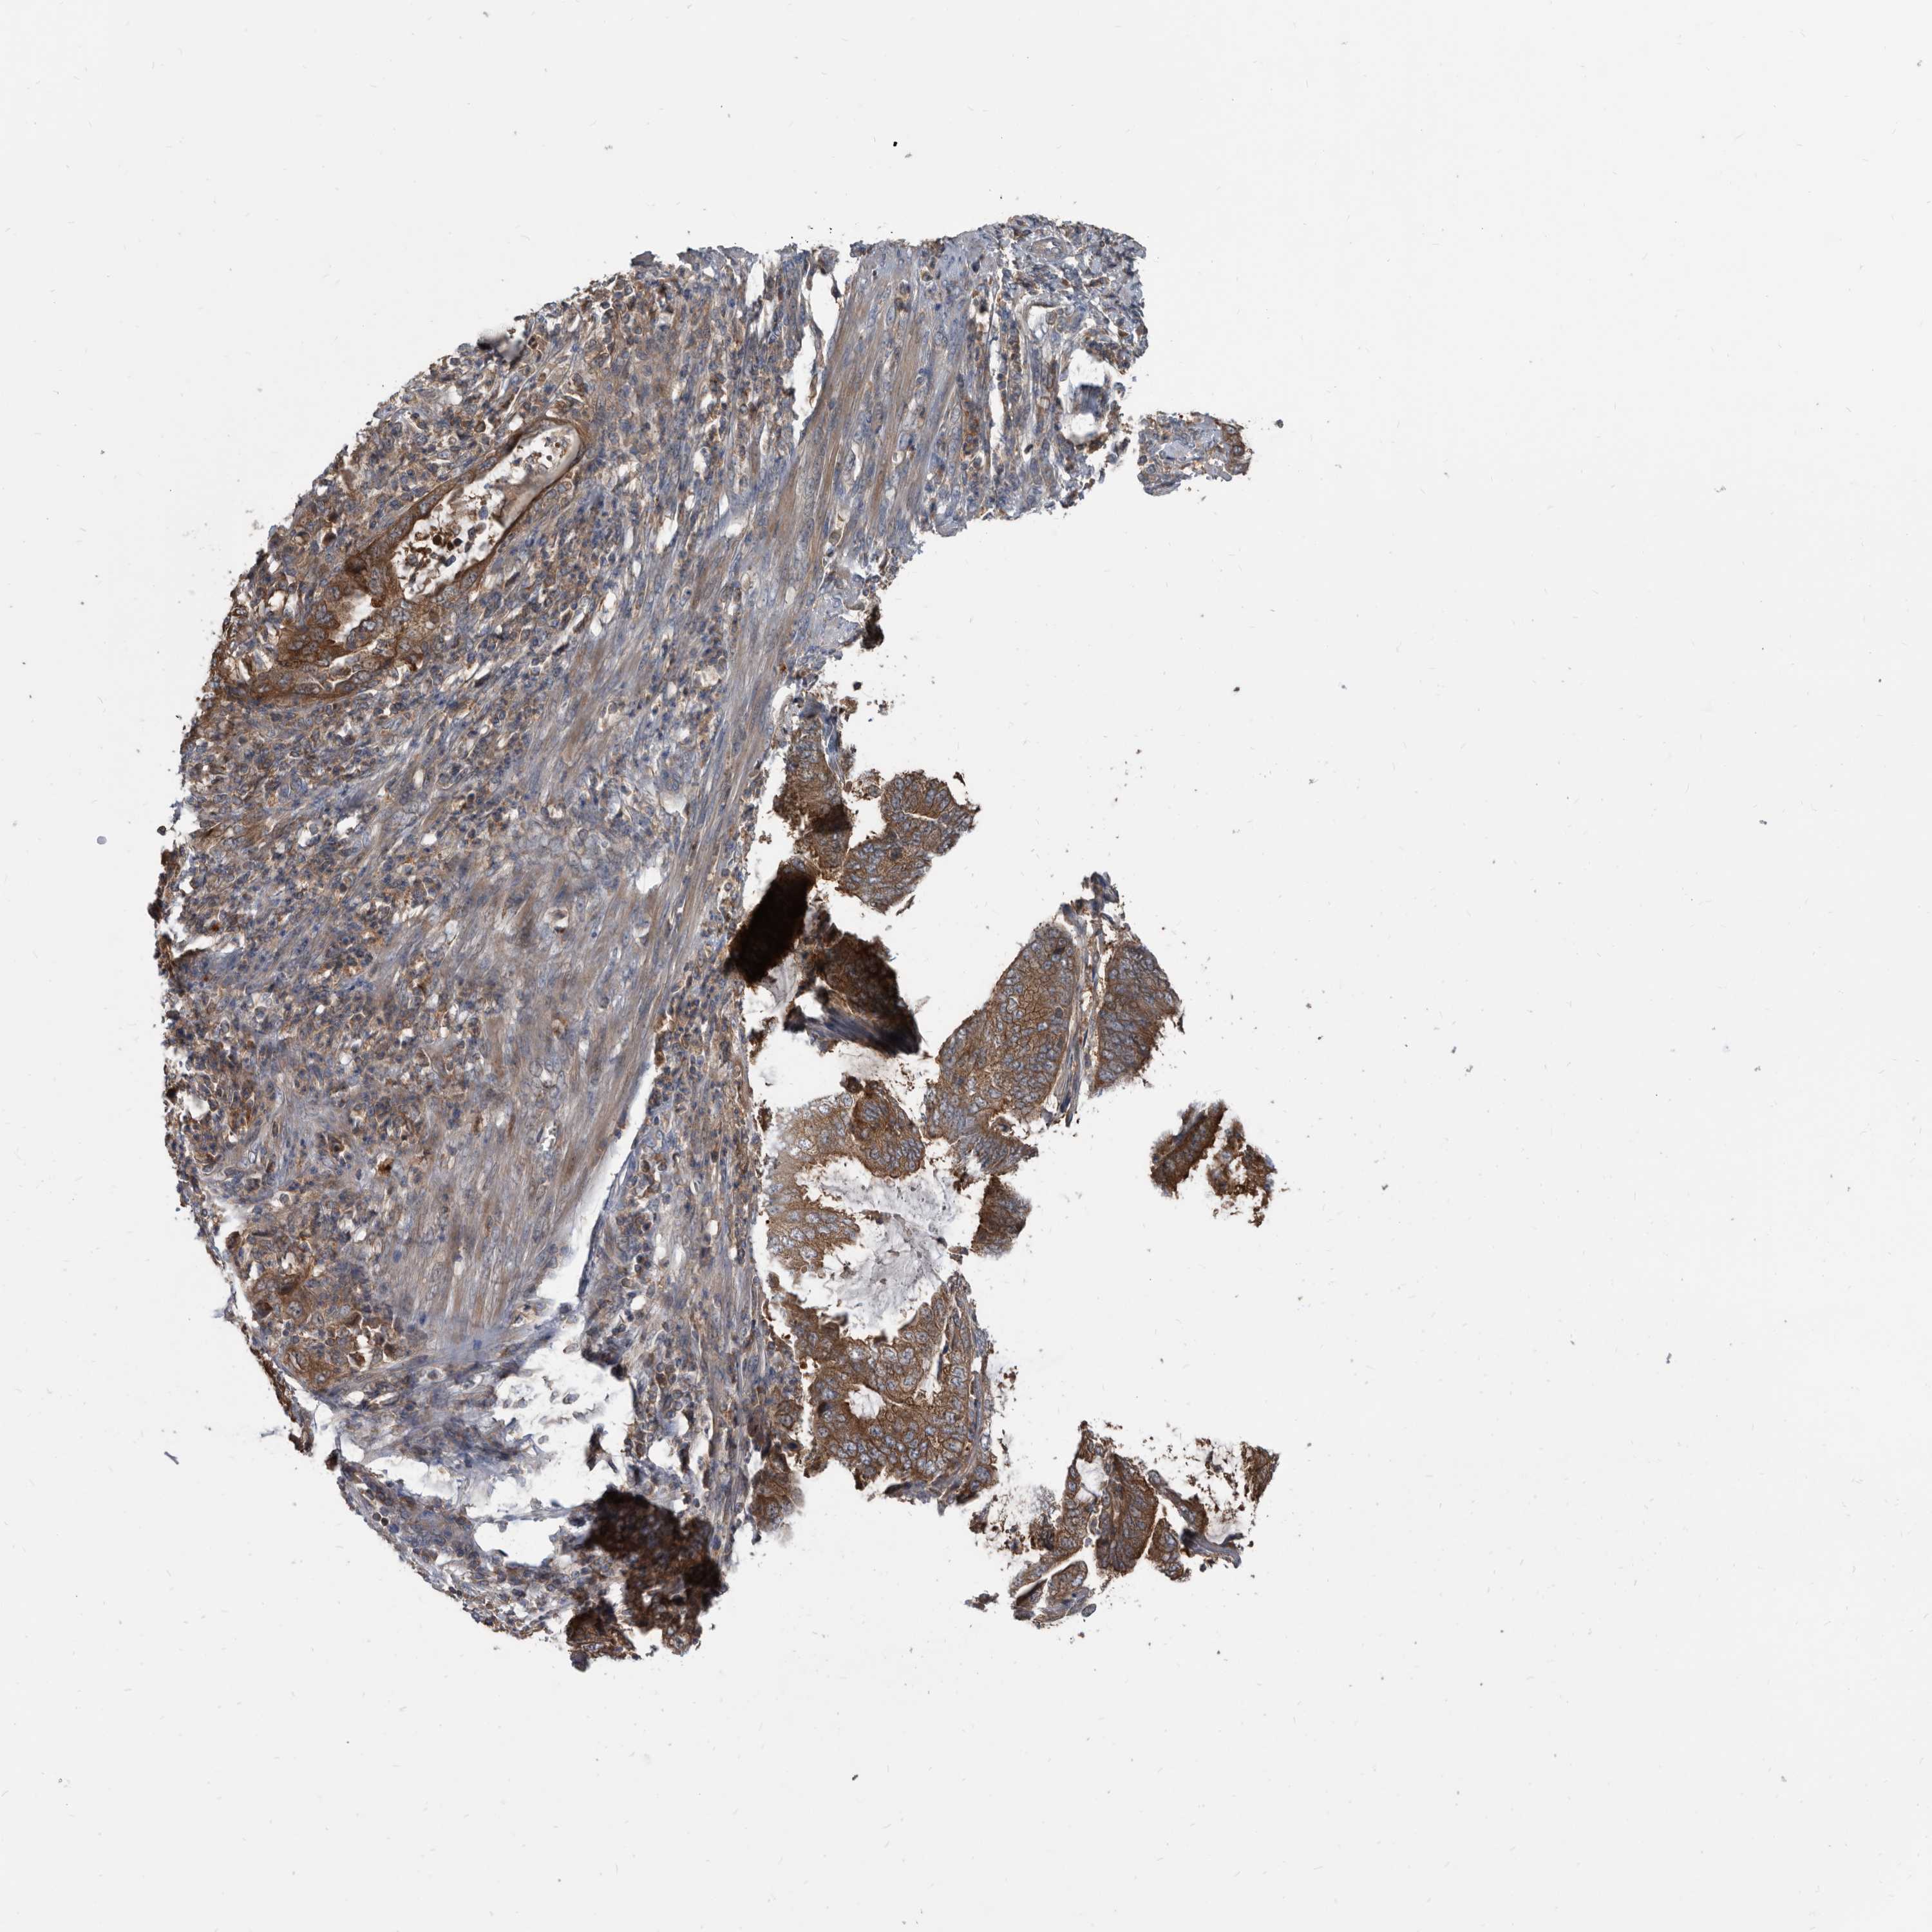

ENDOMETRIAL CANCER - Protein expressioni

A mouse-over function shows sample information and annotation data. Click on an image to view it in a full screen mode. Samples can be filtered based on level of antibody staining by selecting one or several of the following categories: high, medium, low and not detected. The assay and annotation is described here.

Note that samples used for immunohistochemistry by the Human Protein Atlas do not correspond to samples in the TCGA dataset.

Antibody stainingi

Antibody staining in the annotated cell types in the current human tissue is reported as not detected, low, medium, or high, based on conventional immunohistochemistry profiling in selected tissues. This score is based on the combination of the staining intensity and fraction of stained cells.

Each image is clickable and will lead to virtual microscopy that enables deeper exploration of all samples and also displays staining intensity scores, fraction scores and subcellular localization as well as patient and tissue information for each sample.

Antibody HPA029700

Antibody HPA029701

Antibody HPA029702

Antibody HPA029703

Staining

High

Medium

Low

Not detected

Intensity

Strong

Moderate

Weak

Negative

Quantity

>75%

75%-25%

<25%

None

Location

Nuclear

Cytoplasmic/membranous

Cytoplasmic/membranous,nuclear

Adenocarcinoma, NOS

Adenocarcinoma, metastatic, NOS